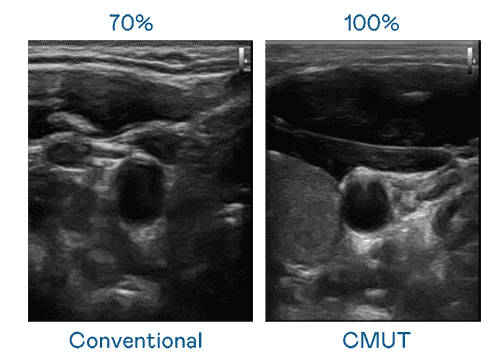

CMUT 技术是一种用电容式微机电元件来产生超音波讯号的技术。。。。与传统 PZT 压电式技术相比,,,,CMUT 频宽增加 30%,,更宽频的超音波讯号让影像解析度大幅提升,,是实现高影像品质医疗超音波扫描、、促进精准医疗发展的关键技术。。。

大频宽带来超清晰影像

超音波影像的解析度高低,,,首先取决于探头能发出的讯号频宽。。龙门国际 CMUT 可提供高清晰的超音波讯号,,提供高频宽、、高灵敏度、、、、影像纹理细节更高的超音波影像,,,协助医护人员缩短影像判读时间及利用精准的医疗影像进行诊断。。